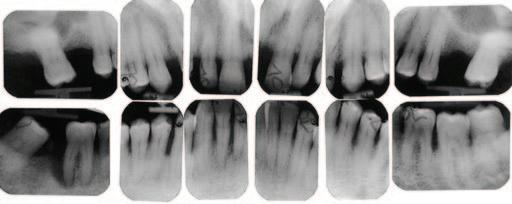

2. Wright, J.T., Crall, J.J., Fontana, M., Gillette, E.J., Nový, B.B., Dhar, V., et al Evidencebased clinical practice guideline for the use of pit-and-fissure sealants: a report of the American Dental Association and the American Academy of Pediatric Dentistry. J Am Dent Assoc 2016; 147 (8): 672-682.e12.

3. Lygidakis, N.A., Garot, E., Somani, C., Taylor, G.D., Rouas, P., Wong, F.S.L. Best clinical practice guidance for clinicians dealing with children presenting with molar-incisorhypomineralisation (MIH): an updated European Academy of Paediatric Dentistry policy document. Eur Arch Paediatr Dent 2022; 23 (1): 3-21.

4. Frencken, J.E. The state-of-the-art of ART sealants. Dent Update 2014; 41 (2): 119-120, 122-124.

CLINICAL TIPS